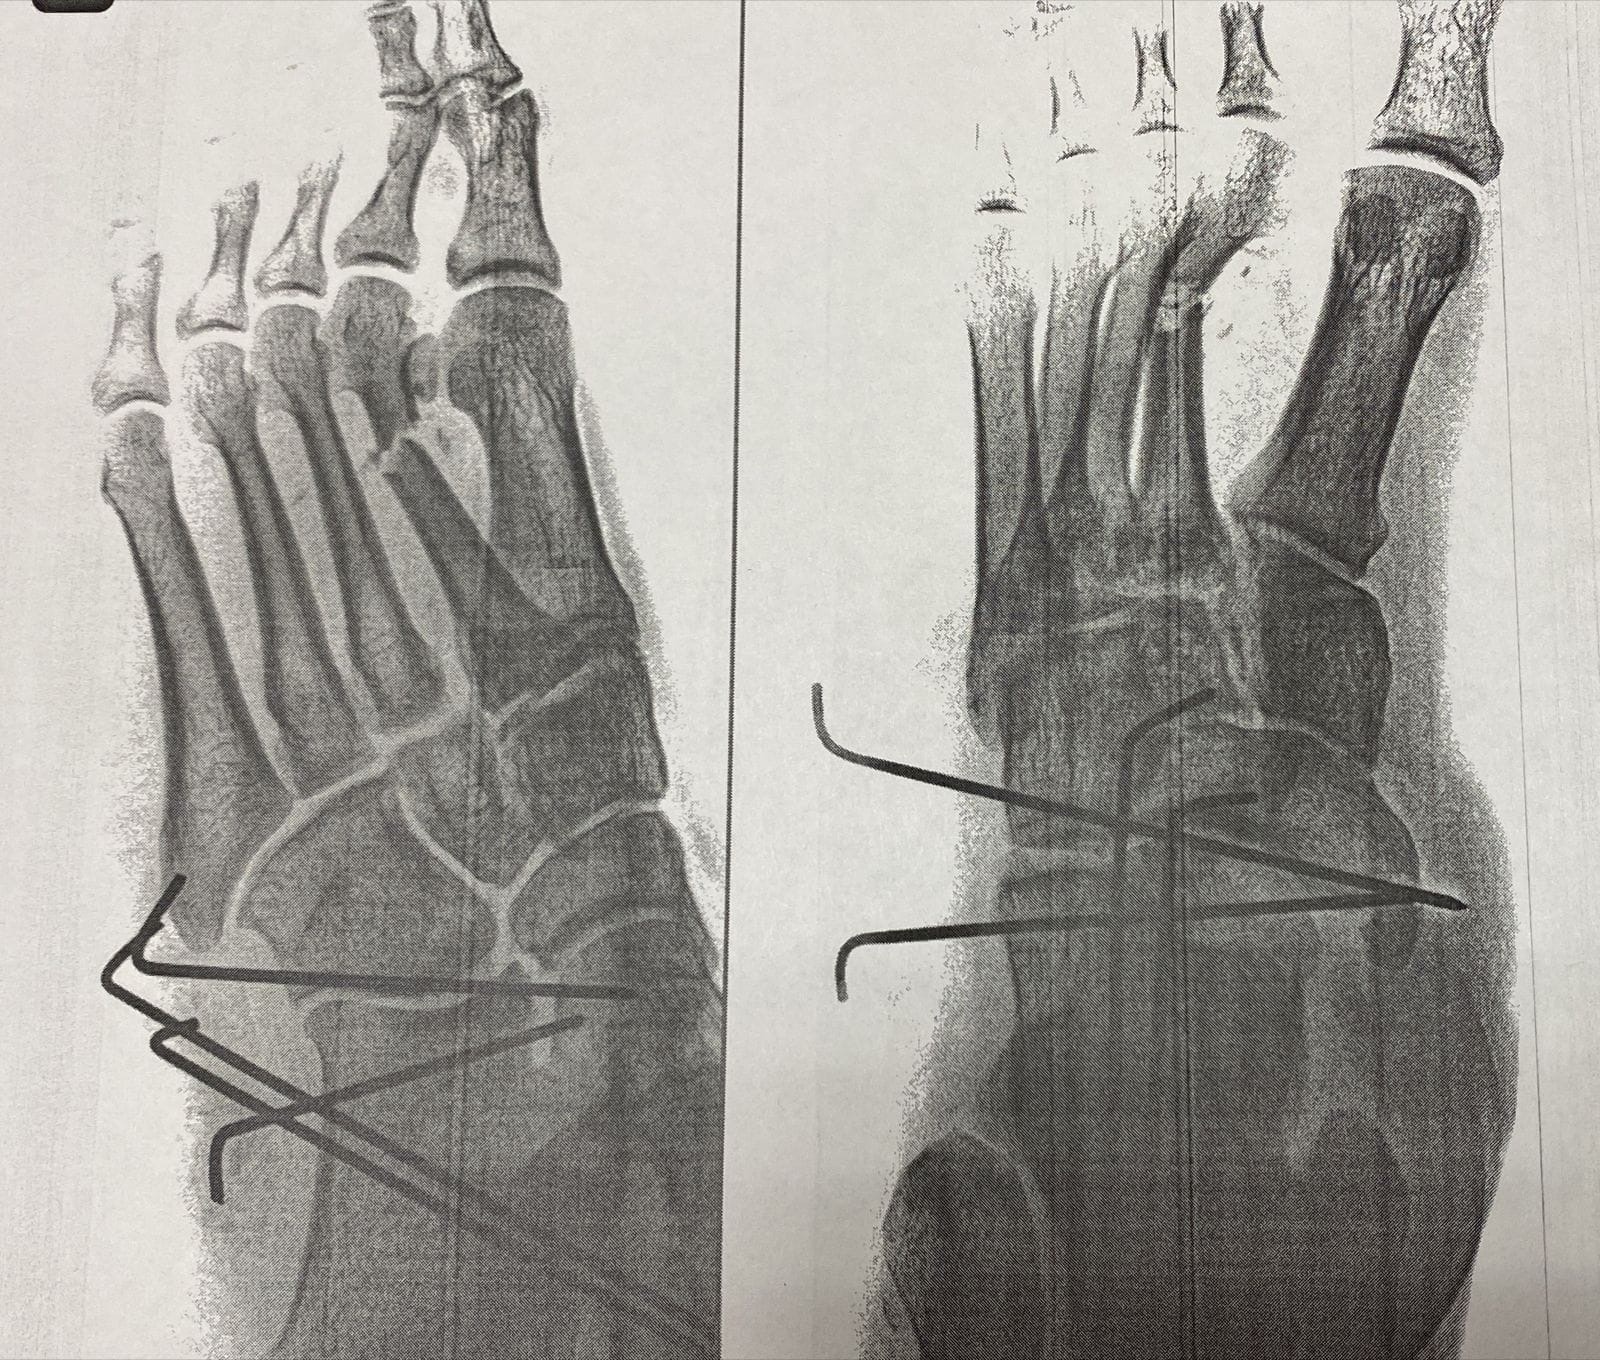

26 октября во 2-е травматологическое отделение Подольской областно клинической больницы поступил пациент после ДТП с тяжелой травмой, фактически размозжением стопы: открытые вывихи во многих суставах, открытые переломы костей, множественные раны.

Дежурный врач отделения Геннадий Старостин его прооперировал. Доктору удалось восстановить анатомию стопы, устранить вывихи, зафиксировать кости стопы спицами, выполнить первичную хирургическую обработку ран. Через несколько дней выполнена дополнительная операция - остеосинтез перелома 3-й плюсневой кости.